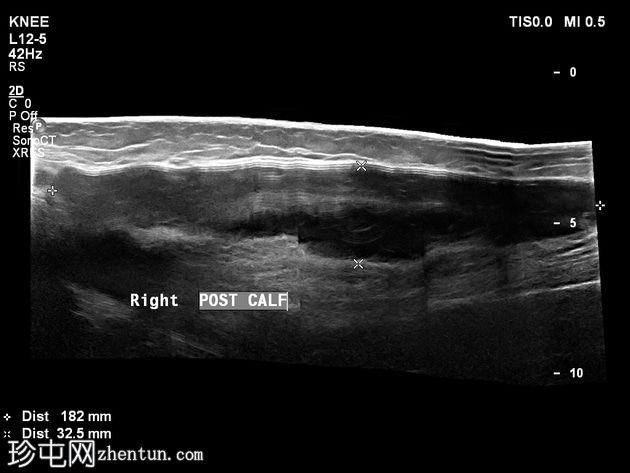

超声

横断面

可见皮下、肌外软性硅胶小腿植入物。植入物包膜局部破裂/撕裂,局部凝胶渗漏,并出现炎症反应,多普勒超声检查显示充血。未见边界清晰或包膜完整的脓肿形成。